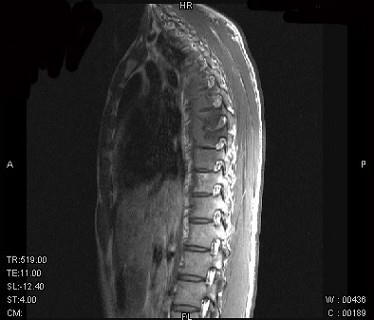

问题 男,21岁,有午后发热,夜间盗汗等,胸部疼痛,活动时加重,休息后减轻,请结合所提供图像,选择最佳答案 ( )

选项 A、骨巨细胞瘤 B、胸椎结核 C、胸椎骨转移 D、胸椎退行性变 E、骨髓瘤

答案 B